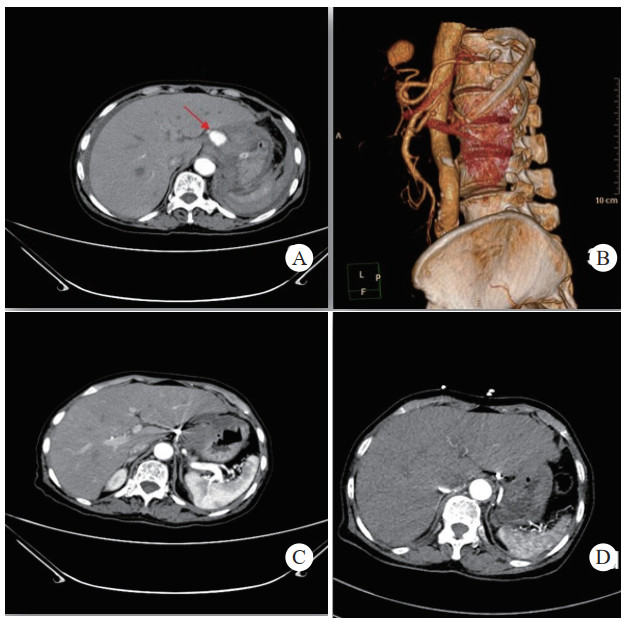

介入栓塞成功率为100%,术中栓塞后即刻复查造影显示,载瘤动脉或假性动脉瘤瘤腔不复显影及未见对比剂外溢,栓塞成功,见图 1(病例1)。

| 注:A、B为患者术前CT增强扫描,示胰腺炎影像,胰头下方血肿影像,中央可见与血管强化方式相同的动脉瘤影像(箭头示),其供血动脉为胰十二指肠上动脉;C为DSA示对比剂充满瘤腔并见对比剂外溢;D为DSA示介入栓塞术后,弹簧圈填满瘤腔及未见对比剂外溢 图 1 病例1术前、术后CT平扫及增强 |